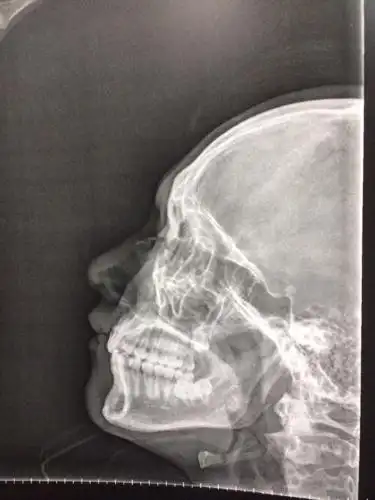

鼻骨折

关于鼻骨骨折歪鼻处理

鼻骨骨折 鼻中隔骨折手术经历 - 知乎